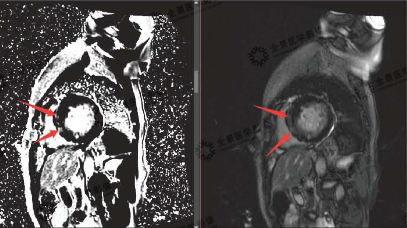

▲A:延迟强化序列 B:电影序列

红色箭头:显示二腔心界面中,前壁、心尖部和后壁环死心肌范围及透壁程度

▲C:延迟强化序列 D:电影序列

红色箭头:中央部短轴显示前壁及前间隔壁、下间隔壁的梗死范围及透壁程度